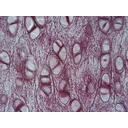

Mapa conceptual de tejido catilaginoso